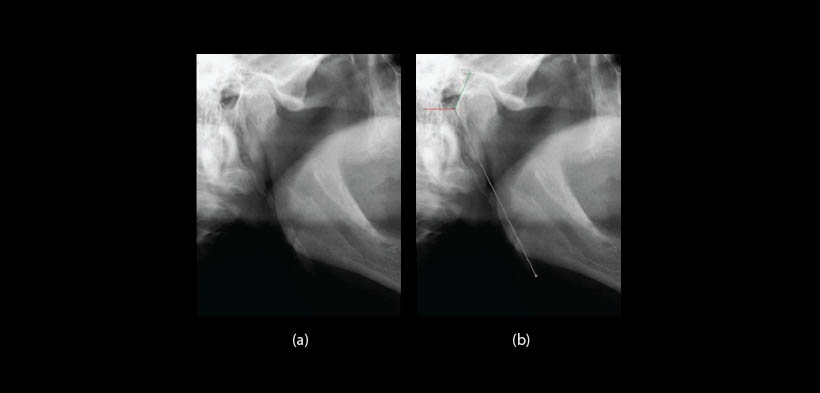

Fig. 3. (a) Radiografía panorámica muestra la apófisis estiloides alargada (tipo I). (b) Manera de realizar la medición de la apófisis estiloides usando la regla de que el software digital trae en sus herramientas (la línea roja muestra el límite inferior del conducto auditivo externo y el verde el límite anterior).